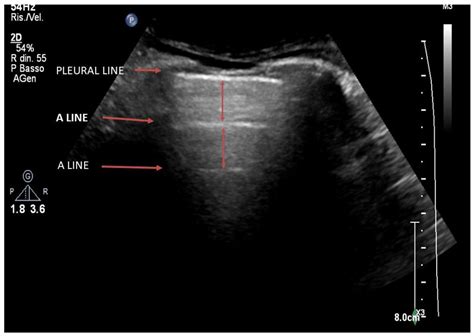

In the context of lung sonography, B Lines Ultrasound patterns are defined as discrete, laser-like vertical hyper-echoic reverberation artifacts. They arise from the pleural line and extend to the edge of the screen, moving in synchrony with lung sliding. Unlike A-lines, which represent normal horizontal reverberations caused by air-tissue interfaces, B-lines signify that the subpleural interlobular septa are thickened by fluid, cells, or fibrous tissue.

When these septa become edematous or infiltrated, they create an acoustic impedance mismatch that traps the ultrasound beam, resulting in the characteristic vertical "comet tail" appearance. Because they move with the visceral pleura, their presence is a highly sensitive marker for the loss of lung aeration.

2. Identify the pleural line—the hyperechoic line moving between the two ribs.

3. Observe the movement of the pleura (lung sliding) to ensure proper positioning.